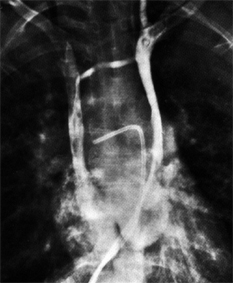

Die weiblich Brust hat die Eigenschaft, im Stehen der Schwerkraft zu folgen, und zwar umso mehr, je schwerer die Brust und je älter die Patientin. Der Port wandert dann mit der Brust nach unten und disloziert den Katheter aus der Vene. An den erweiterten Venen am linken Oberarm und Thorax erkennt man auch eine weitere Komplikation: die Thrombose der Vena subclavia.

Im Röntgen sieht man den dislozierten Katheter und die Kontrastmittelextravasation ins Mediastinum. Dorthin wurde auch das hochgradig gewebetoxische Adriamycin infundiert.